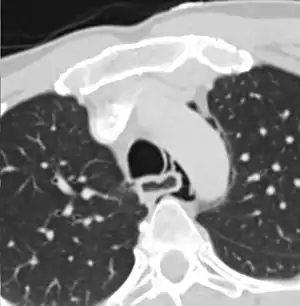

| Axial CT image through the upper chest showing extraluminal air (pneumediastinum) surrounding the trachea and esophagus | |

The diagnosis of Boerhaave's syndrome is suggested on the plain chest radiography and confirmed by chest CT scan. The initial plain chest radiograph is almost always abnormal in patients with Boerhaave's syndrome and usually reveals mediastinal or free peritoneal air as the initial radiologic manifestation. With cervical esophageal perforations, plain films of the neck show air in the soft tissues of the prevertebral space.

Hours to days later, pleural effusion(s) with or without pneumothorax, widened mediastinum, and subcutaneous emphysema is typically seen. CT scan may show esophageal wall edema and thickening, extraesophageal air, periesophageal fluid with or without gas bubbles, mediastinal widening, and air and fluid in the pleural spaces, retroperitoneum or lesser sac.